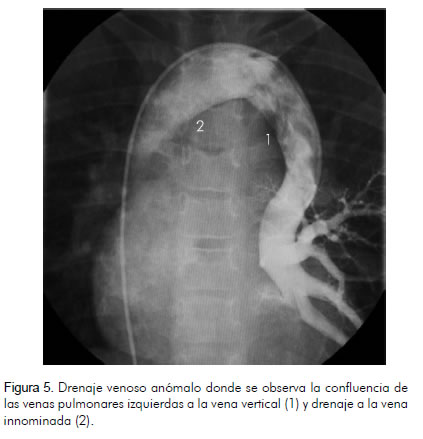

Se indicó cateterismo que reportó conexión anómala parcial de las venas pulmonares izquierdas a una vena vertical que a su vez drena a la vena innominada, Qp/Qs de 1.8:1, y presión pulmonar normal de 29/11/19 mm Hg. Resistencia pulmonar arterial normal con 1,6 unidades Wood (figuras 5 y 6).